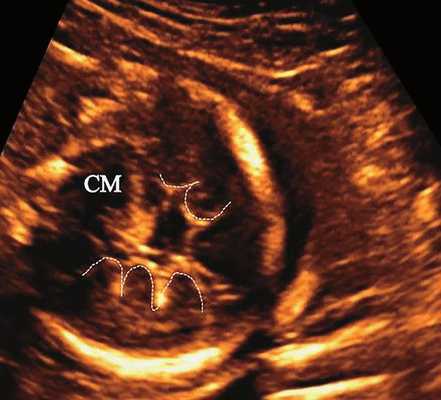

а) Ультразвуковая трехмерная реконструкция (СМ - средний мозг, О - орбита, Ч - червь, М - мозжечок). На плане А показан нижнеаксиальный срез на уровне среднего мозга и орбит, показывающий аномальную бороздчатость медиальной поверхности височных долей (стрелки). Уровень получения этого среза отражен пунктирной линией на плане С. На плане B показан коронарный мозжечковый срез, на котором также отражены выпуклые извилины медиальной поверхности височных долей (стрелки). Пунктирная линия на плане А показывает уровень получения коронарного среза.

б) Представлен косой нижнеаксиальный 2D-срез. Пунктирная линия очерчивает выпуклые извилины с медиальной стороны височных долей (СМ - средний мозг).

б) Нижнеаксиальный ультразвуковой 2D-срез. Уровень среза проходит через средний мозг и орбиты. Стрелки показывают аномально выпуклые извилины медиальной поверхности височных долей (О - орбита)

Во всех представленных наблюдениях проводилось целенаправленное исследование структур мозга плодов для оценки наличия признаков ДВД. Согласно данным литературы, использовались низкие аксиальные и коронарные трансмозжечковые срезы.

В наблюдениях 1-3 наличие изогнутой бедренной кости (по типу "телефонной трубки") (рис. 1в, 2г, 3г) позволяло предположить наличие ТД I типа. Целе направ ленное исследование головного мозга этих плодов в дополнение к описанным скелетным признакам показало и картину ДВД. Была выявлена аномально повышенная бороздчатость и выпуклость извилин нижнемедиальной поверхности височных долей у плодов в наблюдениях 1-3 (рис. 1а, 2б, 3б). Это позволило установить диагноз ТД I типа.

В таких случаях провести дифференциальную диагностику и установить диагноз ТД I типа позволяет обнаружение у плодов при эхографии признаков ДВД, что было показано в представленных наблюдениях 1-3.

ДВД является установленным патогномоничным патологоанатомическим признаком ТД, который отмечается в 97-100% случаев начиная с 18 нед [13]. На рис. 5а отражена нижняя поверхность височных долей мозга с аномальной радиальной бороздчатостью височных долей и в норме. В норме у плодов кора височных долей всегда гладкая (рис. 5б).

В последнее десятилетие были представлены исследования, показавшие возможность выявления ультразвуковых признаков ДВД у плодов с ТД, начиная с 19-20 нед, как проспективно, так и ретроспективно 9. Было показано, что оптимальными срезами для пренатальной диагностики признаков ДВД являются низкий аксиальный срез, включающий средний мозг и орбиты, и коронарный трансмозжечковый срез.

Результативность этих срезов обусловлена тем, что аномальная бороздчатость при ТД бывает выражена, главным образом, в нижних отделах височных долей. Этим же обусловлено то, что эти признаки остаются не диагностированными при стандартных аксиальных скрининговых срезах оценки структур головного мозга плода, которые проходят выше области поражения височной доли при ТД.

Из всех представленных фактов можно сделать вывод, что аномальная бороздчатость нижнемедиальных отделов височных долей в сочетании с признаками летальных скелетных дисплазий является высокопатогномоничным ультразвуковым признаком ТД (I типа) плода.